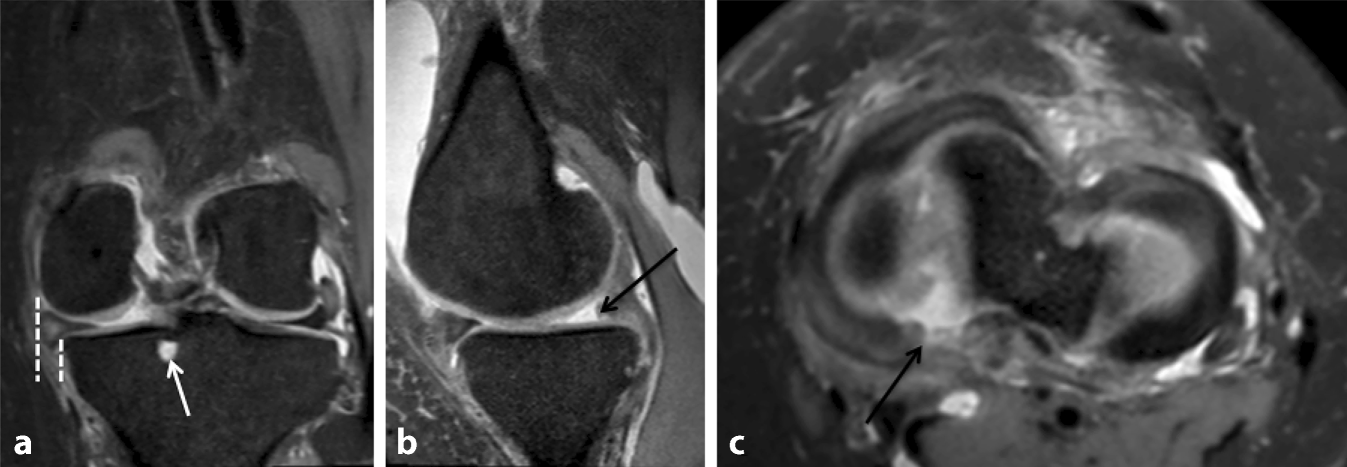

Das MRT zeigt einen dorsalen Wurzelausriss des medialen Meniskus mit der dafür klassischen Trias (Abb. 1): 1) eine Meniskusextrusion von > 3 mm in der Koronalebene 2) ein „ghost sign“ (Fehlen des Meniskus auf mehr als 3 aufeinanderfolgenden Sagittalschnitten), 3) eine subchondrale Knochenzyste im Bereich des dorsalen Wurzelansatzes. Als weiteres Zeichen findet sich eine intrameniskale, T2-hyperintensive Hypertrophie des Meniskuskörpers, hinweisend auf einen degenerativen Ursprung.

Abb. 1

Das MRT zeigt eine hintere Wurzelabrissstelle des medialen Meniskus. In der koronalen Ebene (a) beträgt die Extrusion des medialen Meniskus mehr als 3 mm (gepunktete Linien), und am Ansatz der Wurzel ist eine Knochenzyste (weißer Pfeil) zu erkennen. In der Sagittalebene (b) ist das Geisterzeichen zu erkennen (Fehlen des Meniskus bei 3 aufeinanderfolgenden Schnitten, schwarzer Pfeil). In der axialen Ebene (c) kann eine Wurzelablösung beobachtet werden